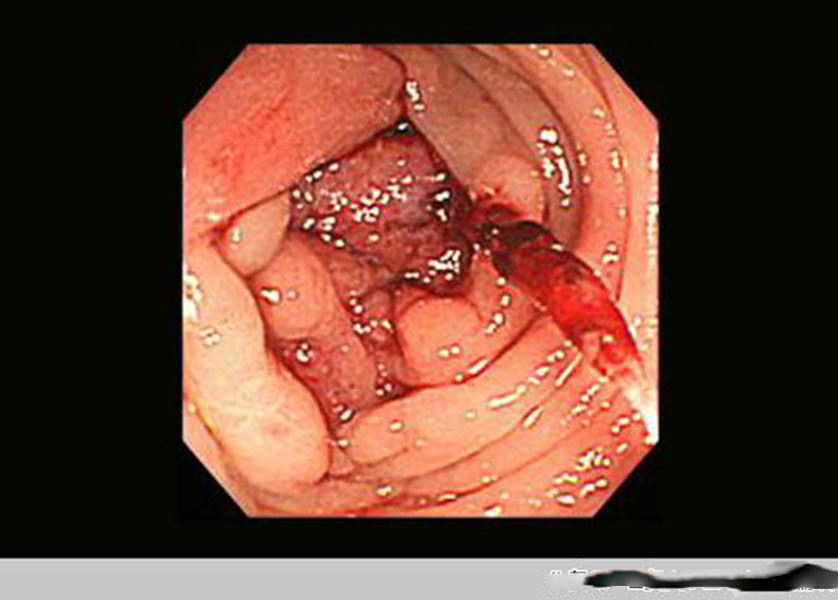

腸腫瘤圖片

腫瘤腸腫瘤真實

腫瘤腸腫瘤病變真

腫瘤病變腸腫瘤

直腸腸腫瘤過程

直腸腸腫瘤後期